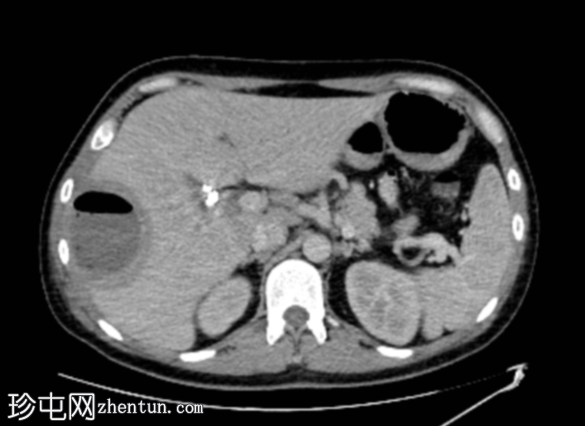

轴位增强扫描

3.png

动脉期

增强扫描图像显示囊肿边缘强化,周围可见晕环,呈双靶征。

该患者近期行胆囊切除术及胆总管支架置入术,近期主诉右上腹疼痛及发热。影像学表现符合医源性化脓性肝脓肿介入治疗后的典型特征,右肝叶囊性病变可见管腔内气体和气液平面,增强扫描后边缘强化,并可见经典的双靶征。患者接受了超声引导下经皮穿刺引流术治疗。遗憾的是,培养结果尚未公布。

“双靶征”表现为:中央低密度病灶(充满液体)周围环绕着高密度内环和低密度外环。